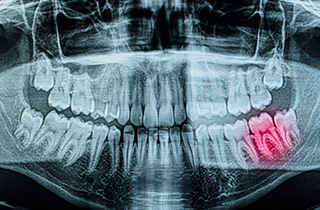

Caries treatment for decay detected on X-ray imaging

-

Pulpitis

Inflammation has progressed to the dental pulp, causing severe pain that may become difficult to tolerate.

Root Canal Treatment + Crown

Pulp Necrosis

The tissue inside the tooth has become necrotic, and bone around the root is gradually lost due to infection.

Extraction + Implant